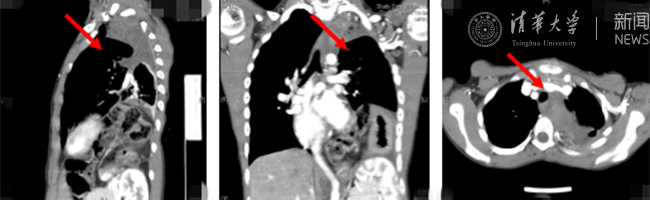

清华新闻网8月30日电(通讯员 杨峰)如图中所示,本是正常人心脏、左肺的位置,被发于神经鞘的巨大肿瘤占据,导致一位刚满12岁的男孩胸痛、咳嗽、呼吸困难。近日,北京清华长庚医院神经外科与胸外科联手,由神经外科王贵怀主任主刀,成功为男孩切除胸腔巨大神经鞘肿瘤。

患者胸腔内巨大的肿瘤。

半年前,患者经常会出现胸痛、咳嗽和呼吸困难,在当地医院检查发现左侧胸腔巨大占位,左肺及心脏明显受压。王贵怀大夫接诊,仔细查体了解病情,并反复认真阅片后,认为左侧胸腔巨大肿瘤来自于胸椎椎管内,神经鞘瘤可能性大。该肿瘤体积巨大,占据绝大部分胸腔空间,压迫左肺、纵隔大血管及膈肌。